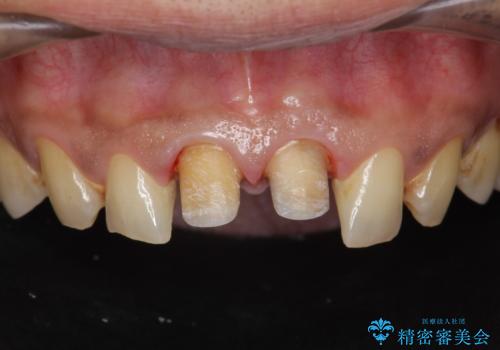

歯ぐきからの出血 膿が出る 前歯根管・セラミック治療

- 40代男性

- 体調により前歯部の歯ぐきから出血や膿が出ることの改善を求めて来院されました。

X線写真より、根尖部に透過像が認められ根管治療・ファイバーコア築盛・セラミッククラウンの作製が必要な状態です。